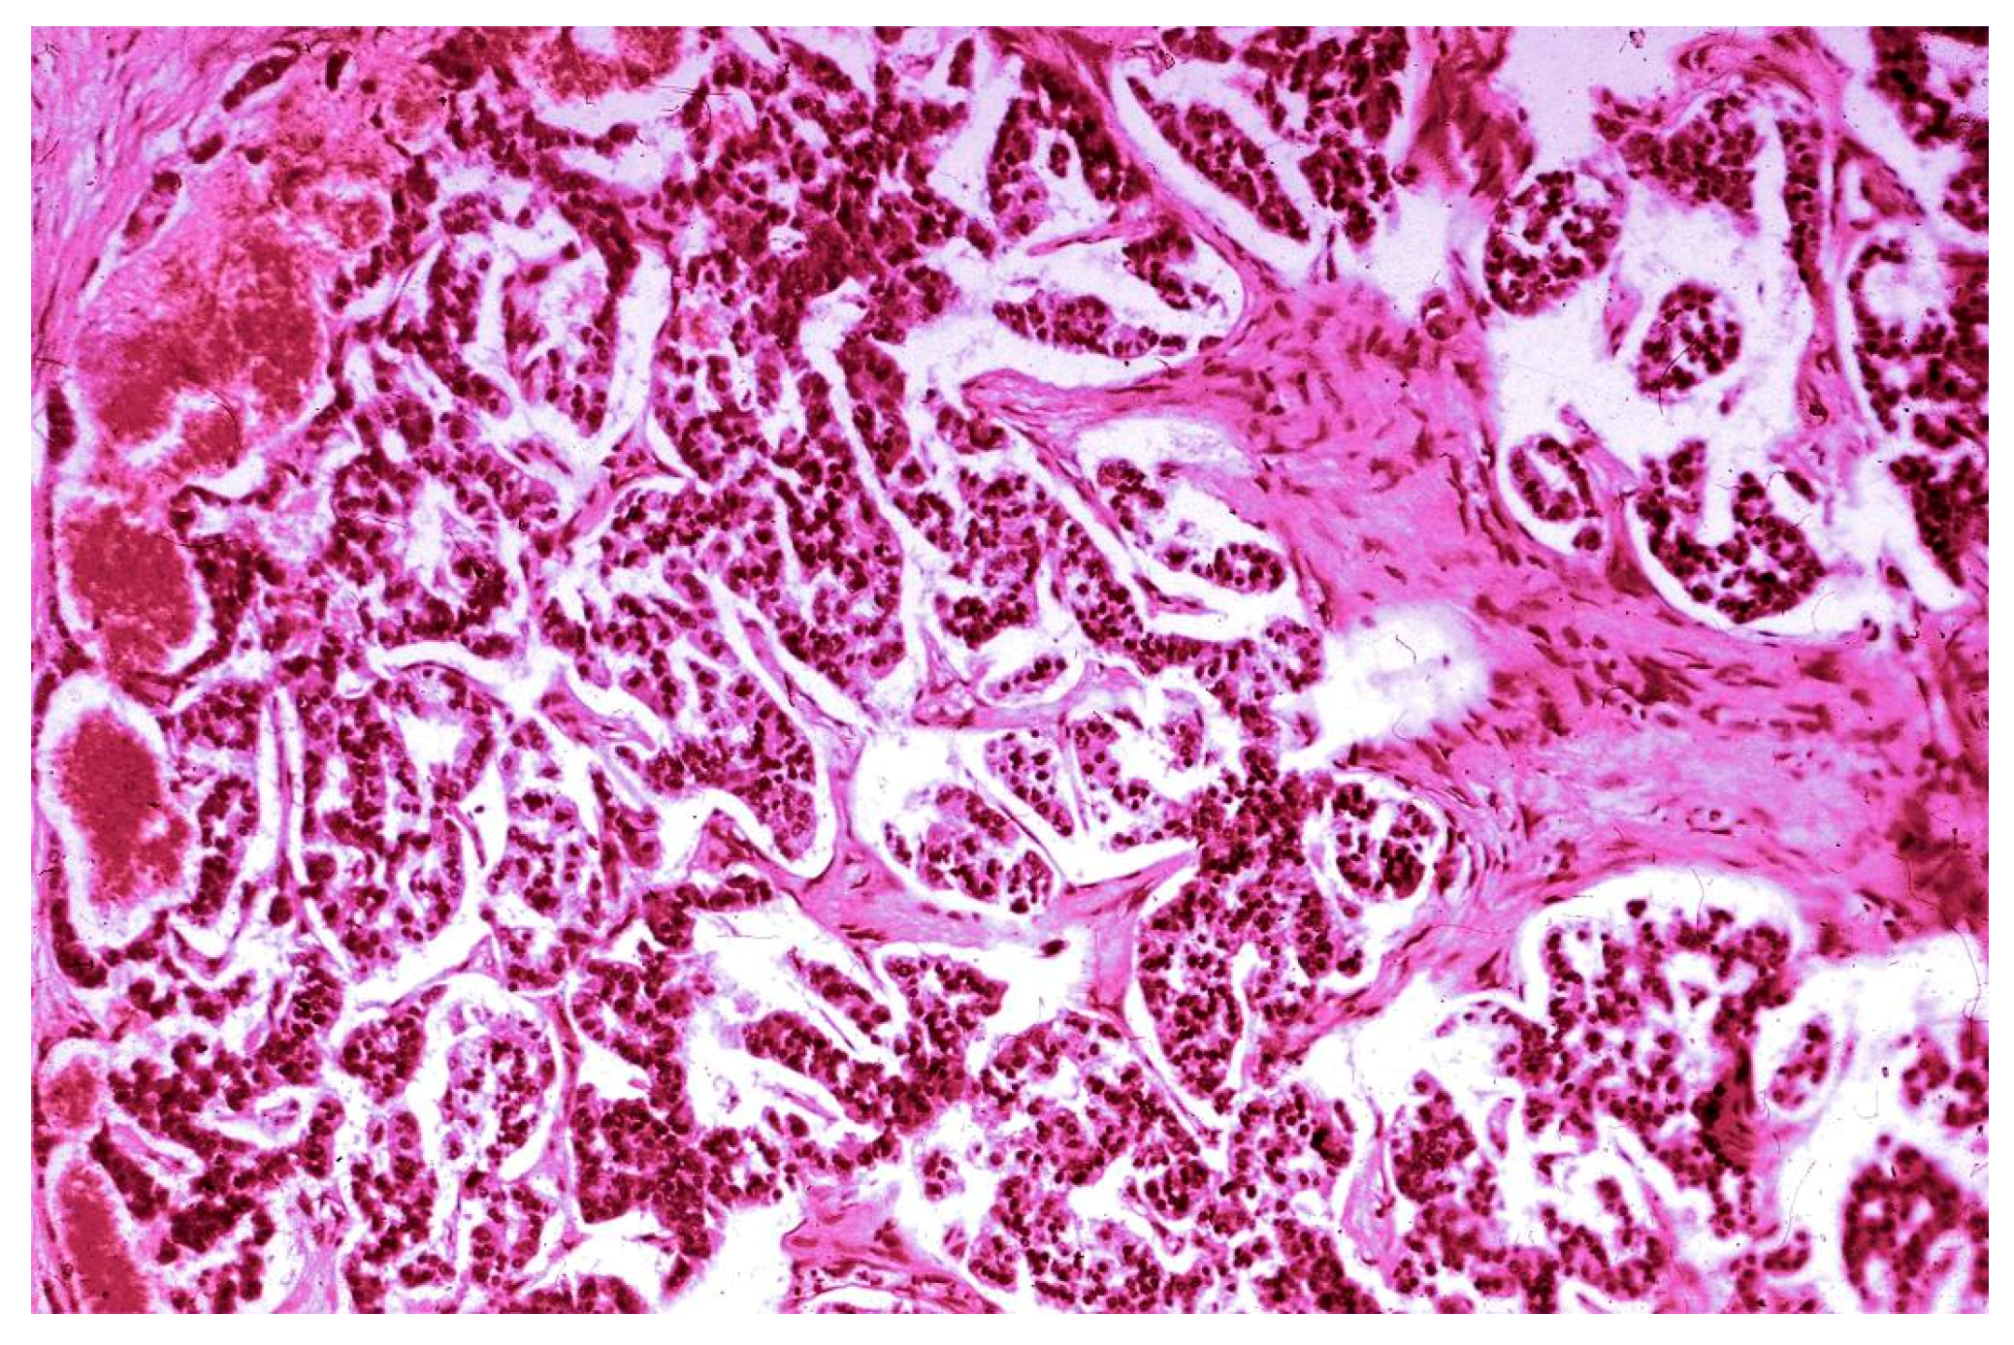

3.2. Histopathological Findings